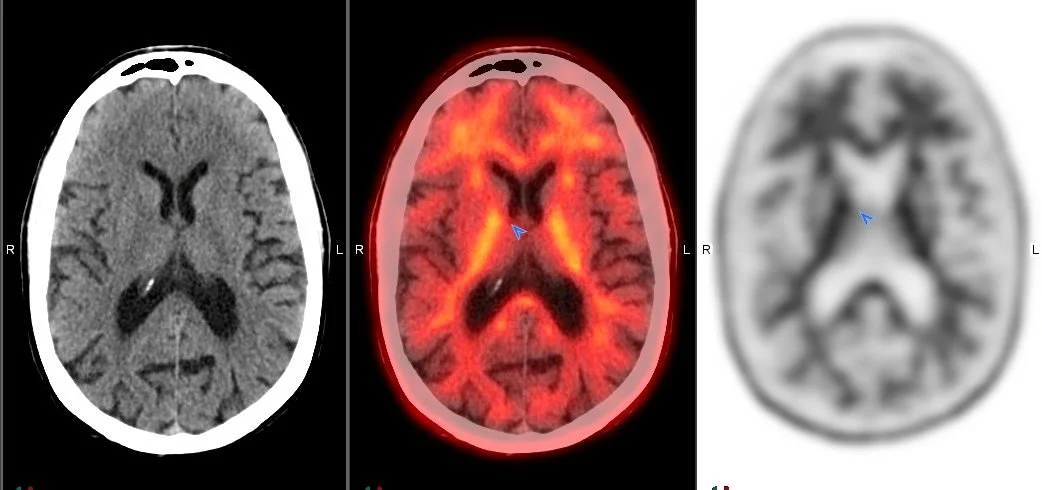

PET/CT is used to perform scans of the brain which provide information for assessing several neurological diseases including Alzheimer’s Disease, Parkinson’s Disease, Huntington’s Disease, and dementias. A PET/CT scan of the brain involves a radiopharmaceutical that helps to create a normal versus abnormal map of brain functionality. Mapping distinctive patterns of metabolism assists physicians in accurately diagnosing patients and treating them appropriately.

PET/CT scans are also used in cases of epilepsy, to help localize the seizure focus in patients with seizure disorders, and in stroke, to evaluate the extent of stroke damage and to monitor recovery following therapy.